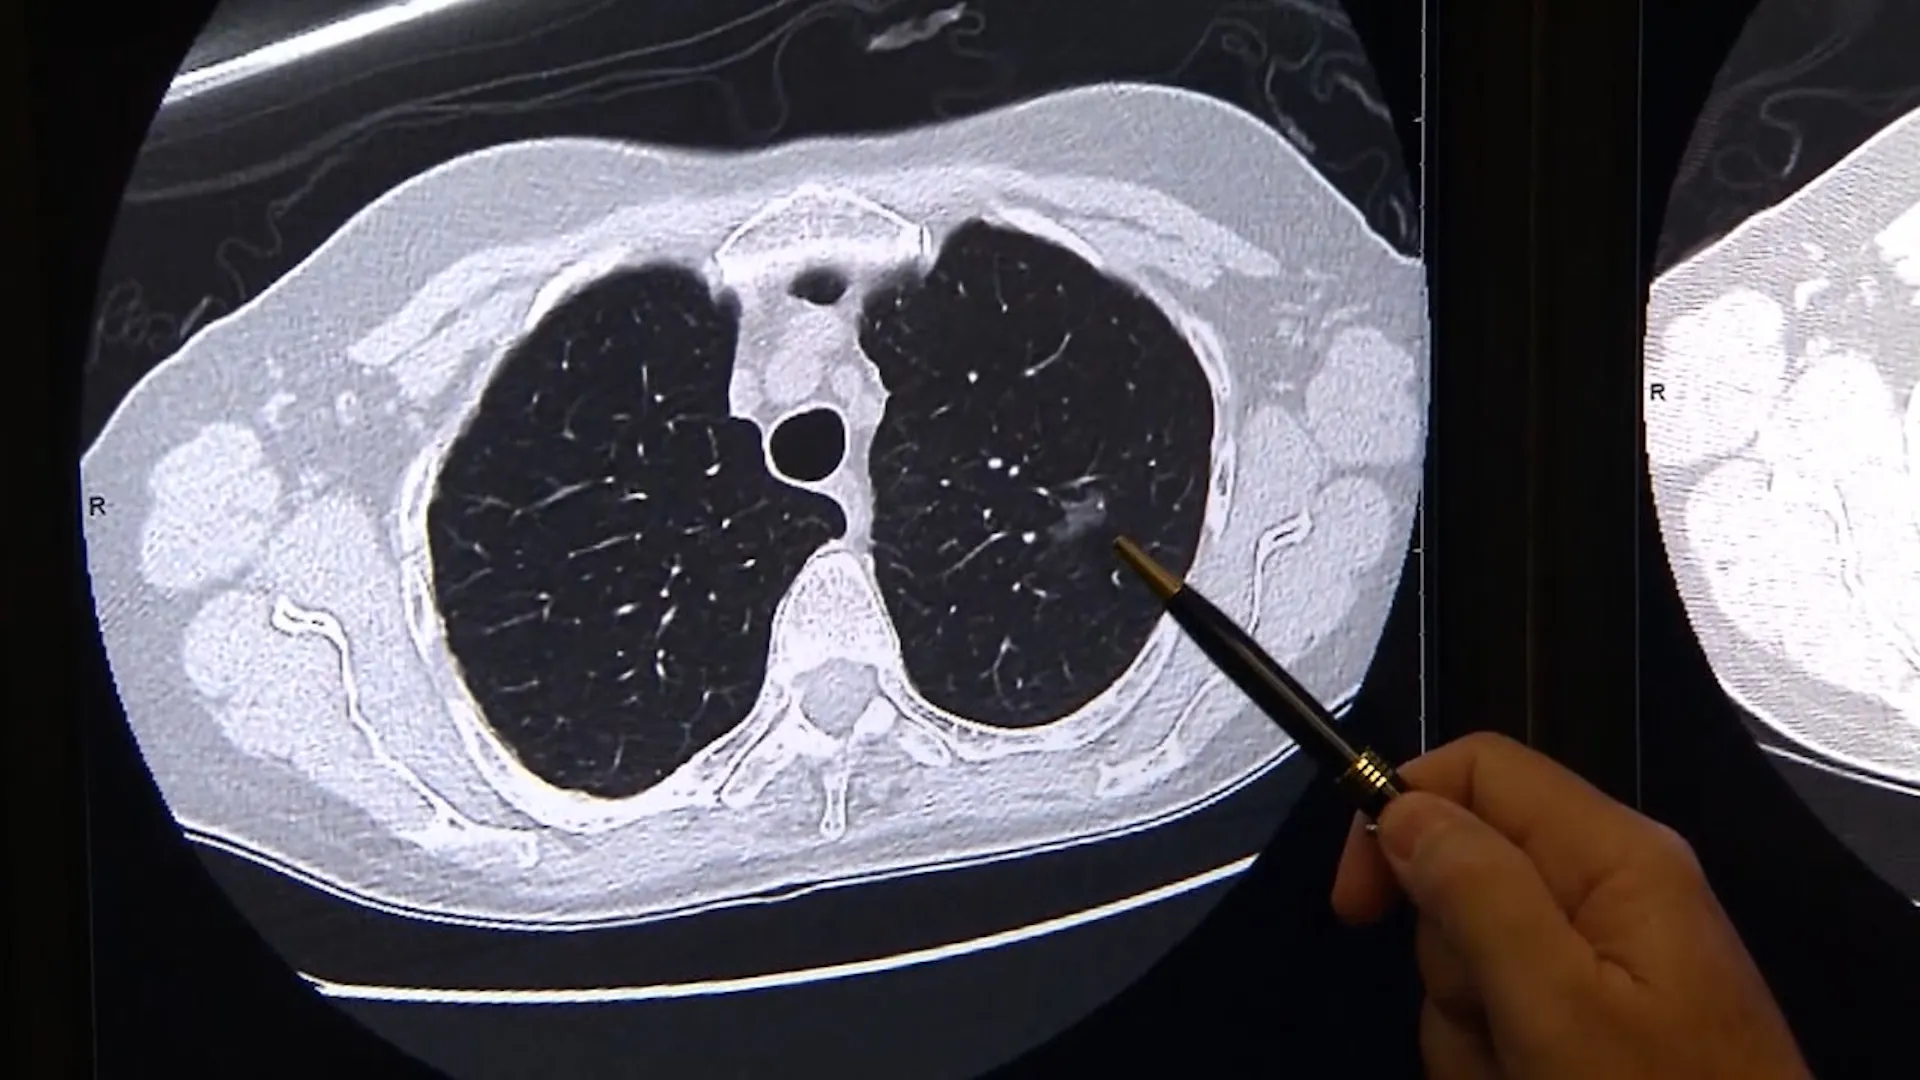

肺がんは日本におけるがん死亡原因の上位を占める重大な疾患であり、その中でも肺がん ステージ 4は最も進行した段階を指します。ステージ4と診断されると、多くの患者さんやご家族が強い不安を感じますが、近年は医療の進歩により治療選択肢が大きく広がっています。分子標的治療薬や免疫チェックポイント阻害薬の登場により、従来よりも長期生存が期待できるケースも増えています。…

肺がんは、日本におけるがん死亡原因の上位を占める重大な疾患です。特に「肺がん 症状」は初期段階では目立ちにくく、風邪や気管支炎と誤認されやすいことから、発見が遅れるケースも少なくありません。そのため、早期警告サインを正しく理解し、適切なタイミングで医療機関を受診することが極めて重要です。…